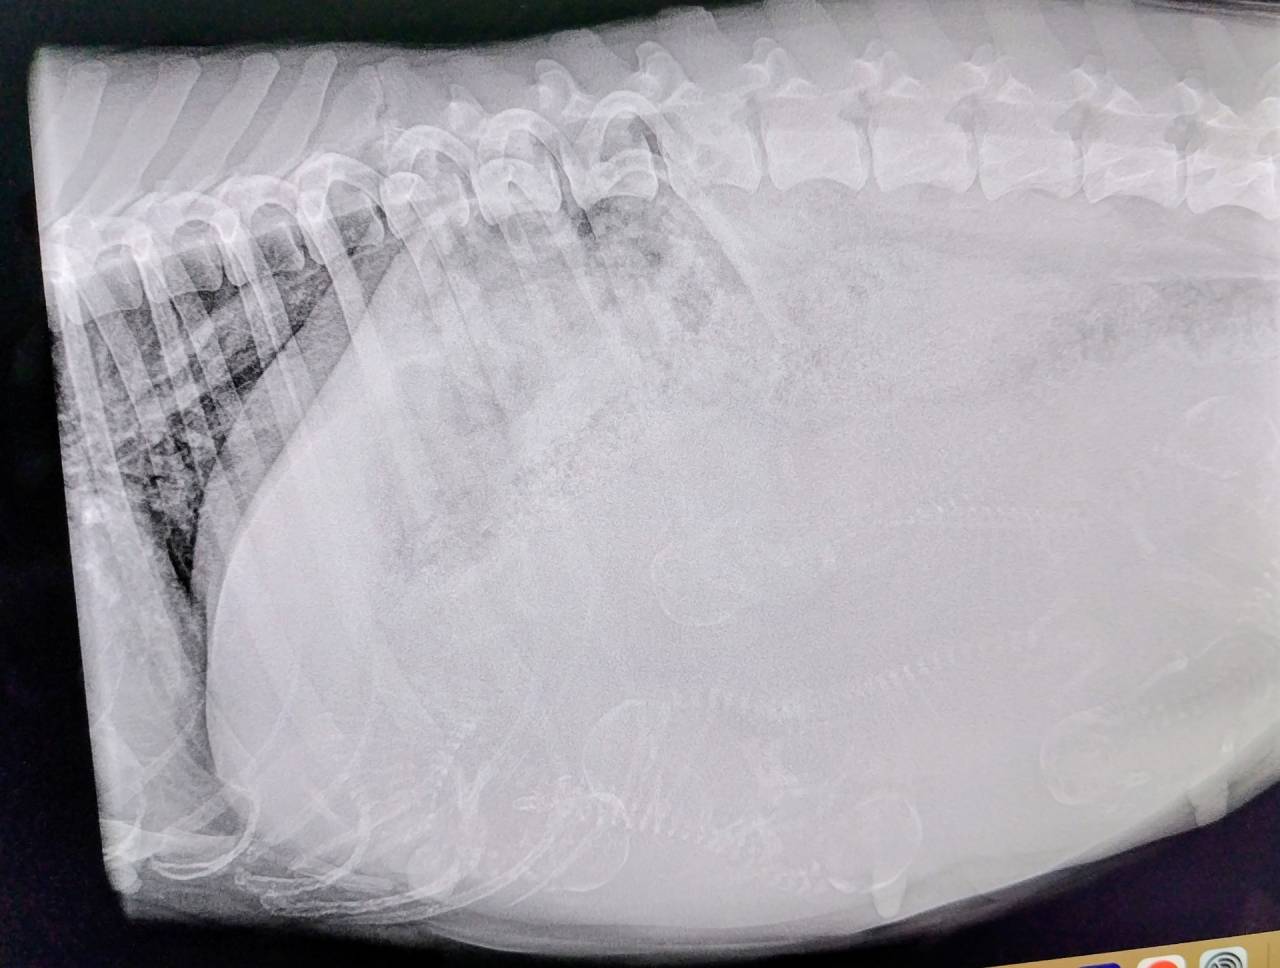

アリスは予定日1週間前ということで、頭数確認のためレントゲン検査。アリスは通いなれた病院で何の問題もなく診察室へ。いつものように手のかからない子で、看護師さんや先生にいい子撫でしてもらってご満悦。体重の増加は約4㎏、7頭確認できました。今回はプラスαはないかもですね。頭の大きさや産道も見ていただいて問題はないそうです。アリスは4歳、来日してから1回お休みをして4回目の出産になります。まだまだ元気で頑張ってくれています。ここまで来たらとにかく安産で無事出産を願うだけです。週末から来週初めくらいかな?